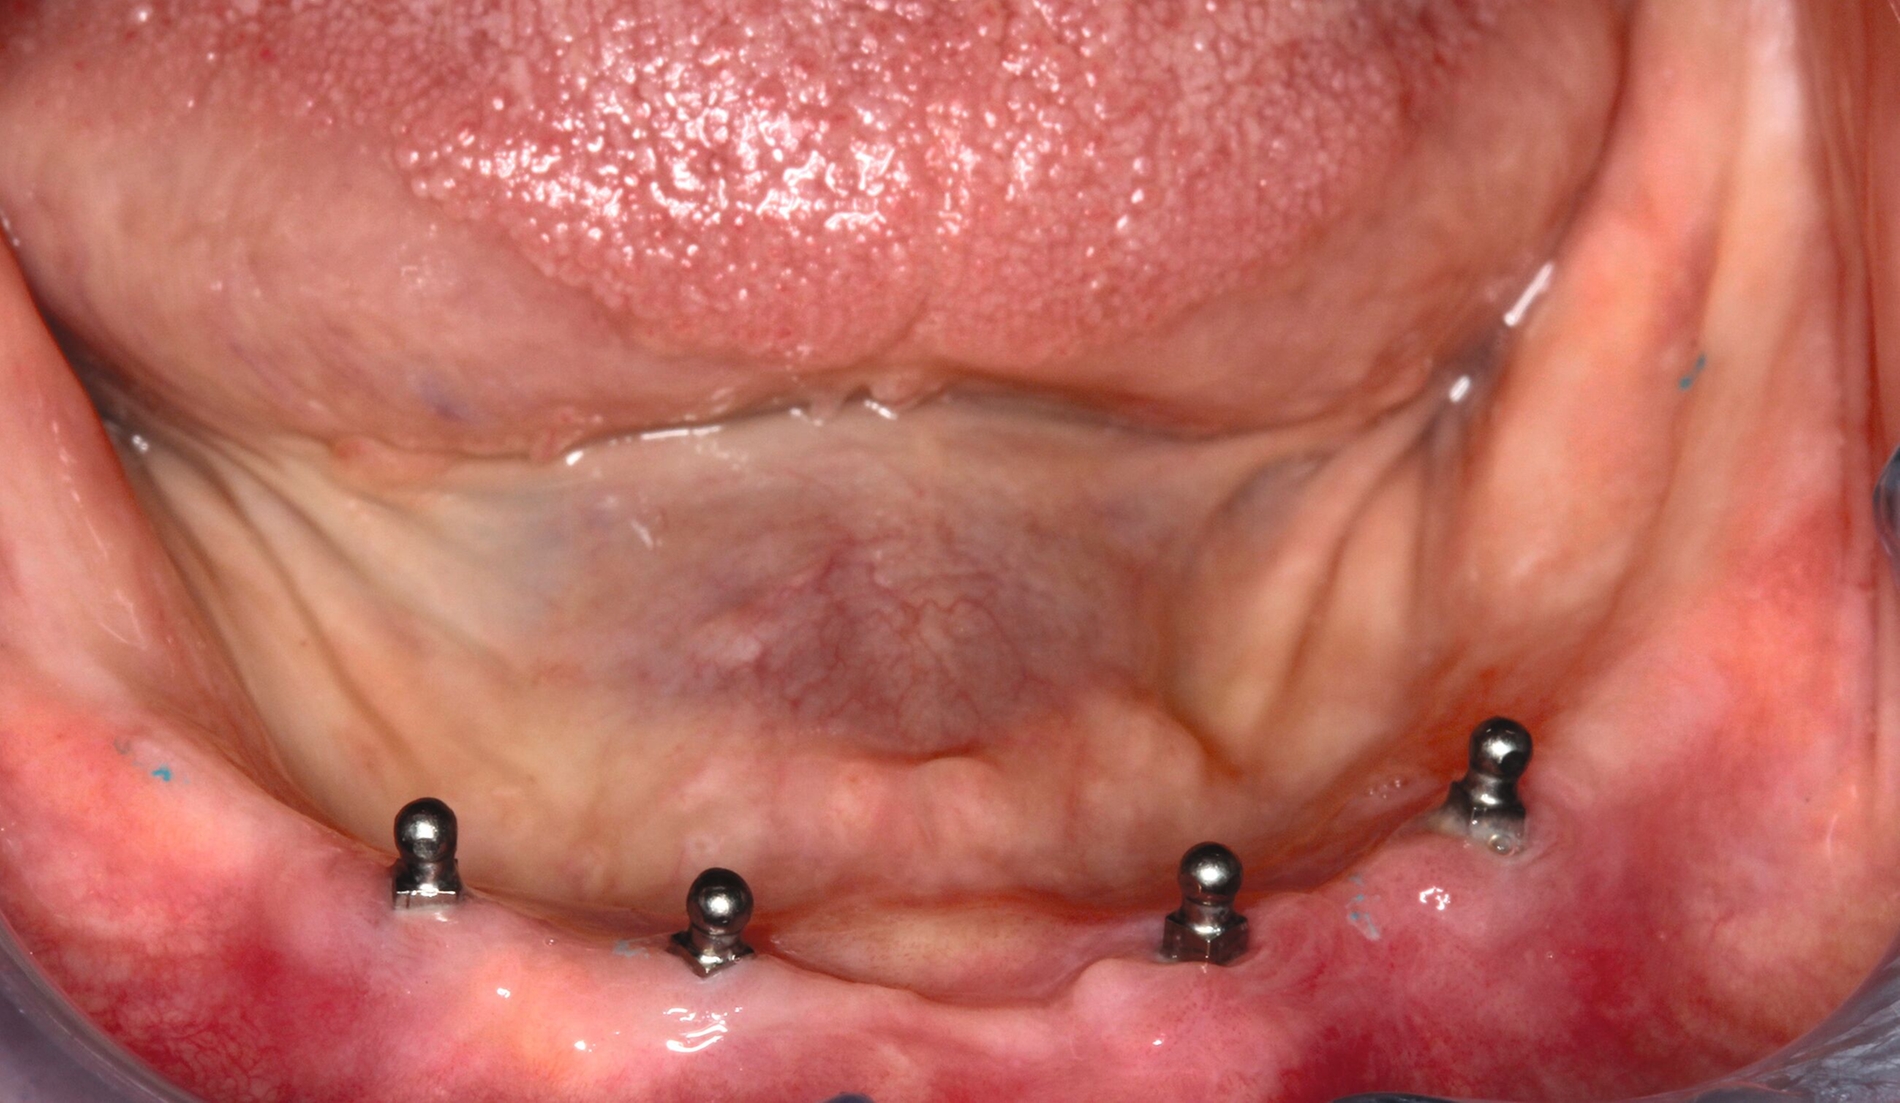

Zur Prothesenstabilisierung werden seit Ende der 1990er-Jahre Miniimplantate mit einem Durchmesser von weniger als 3 mm verwendet. Empfohlen werden hierfür vier interforaminale Implantate im Unterkiefer und sechs Implantate zwischen den Sinus maxillares im Oberkiefer (Abbildung 4) [Lemos et al., 2017]. In der Regel liegt der Implantat-Durchmesser zwischen 1,8 und 2,5 mm [Schiegnitz und Al-Nawas, 2018]. Sie sind deshalb bis auf wenige Ausnahmen [Morneburg und Proschel, 2008] einteilig [Jawad und Clarke, 2019]. Eine vollkommen belastungsfreie Einheilung ist deshalb nicht möglich [Mundt et al., 2015]. Sie eignen sich für sehr schmale Kieferkämme, bei denen anderenfalls Augmentationen notwendig gewesen wären. Viele Anwender inserieren Miniimplantate erfolgreich transgingival („flapless“) [Marcello-Machado et al., 2018]. Der Autor dieses Beitrags empfiehlt jedoch sicherheitshalber die Bildung eines kleinen Mukoperiostlappens zur Kontrolle der Insertionsstelle („mini-flap“) und die transgingivale Insertion nur bei breiten Kieferkämmen oder nach dreidimensionaler Bildgebung zusammen mit einer Bohrschablone für eine geführte Aufbereitung.

Mittlerweile gibt es zahlreiche Hersteller, die Miniimplantate in ihr Produktportfolio aufgenommen haben. Am häufigsten werden Kugelköpfe zur Verankerung auf Miniimplantaten genutzt [Marcello-Machado et al., 2018], aber es gibt dafür auch eine Reihe anderer Patrizen- und Matrizenformen wie Magnete, Locatoren oder ähnliche Verankerungen und sogar Stege [Leles et al., 2022; Lemos et al., 2017]. Beispielhaft zeigt die Abbildung 5 eines der ersten Miniimplantat-Systeme, dass inzwischen in zahlreichen Studien überprüft wurde [Enkling et al., 2019, Lemos et al., 2017, Shatkin und Petrotto, 2012]. Die Länge beginnt bei 10 mm, hauptsächlich werden jedoch 13 mm lange, 1,8-mm-Miniimplantate im Unterkiefer und 2,4-mm-Miniimplantate im Oberkiefer verwendet. Die Aufbereitungstiefe mit dem dünneren 1,1-mm-Bohrer richtet sich nach der Knochenqualität. Durch das selbstschneidende Gewinde erlangt das Implantat ähnlich einer Holzschraube seine primäre Stabilität. Erst bei einem finalen Eindrehmoment ab 35 Ncm aller Implantate pro Kiefer sollte eine Sofortbelastung erfolgen. Dafür werden die Matrizen (Housing mit einem O-Ring aus Nitrilgummi) entweder intraoral oder über eine Abformung in die Prothese einpolymerisiert. Ist das Eindrehmoment geringer, sollte die Prothese zunächst für drei Monate weichbleibend unterfüttert werden [Mundt et al., 2015]. Die Kugel nutzt seitlich nicht ab, da der O-Ring bei der Protheseneingliederung über den Äquator gleitet und darunter auf dem Insertionsvierkant verbleibt. Die Haftkraft ändert sich auch nach Jahren nicht, wenn der O-Ring bei Abnutzung ausgetauscht wird [Abou-Ayash et al., 2019].